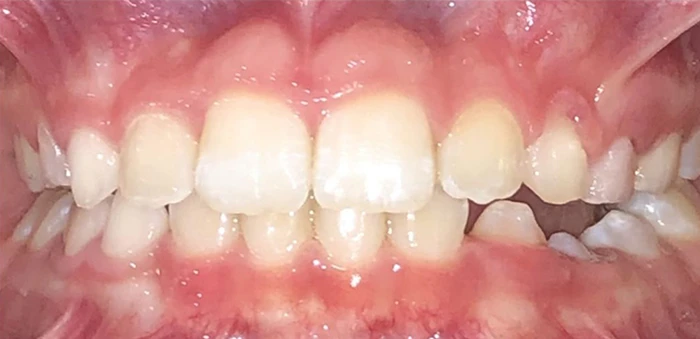

Actual Patient: Samuel

Samuel before1 img Samuel after1

Severe “Overbite”, BUCK TEETH, Narrow Jaws, Severe Deep Bite, Blocked out teeth

img Samuel before2 1 img Samuel after

Front View

Top View

Right & Left Sides